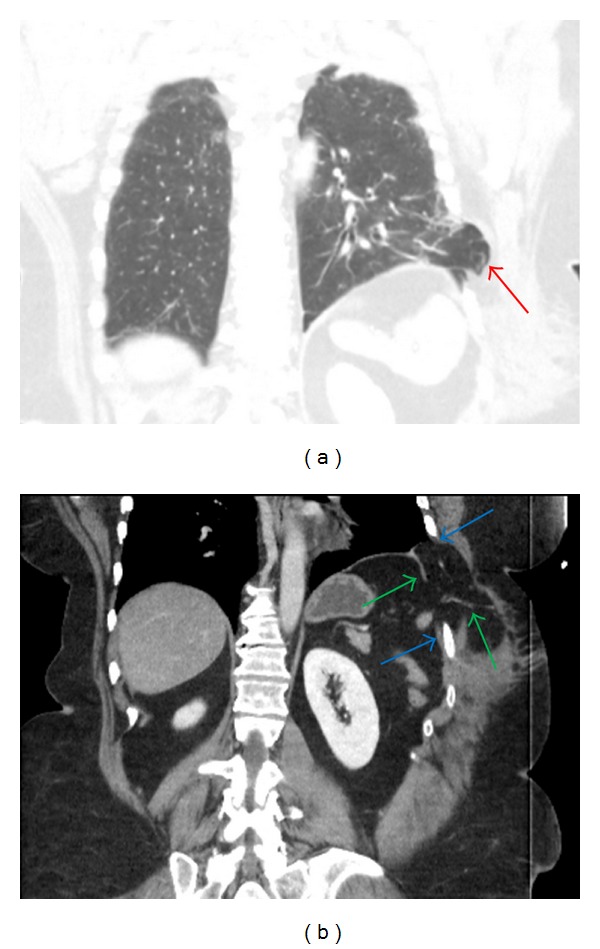

Figure 2.

Axial CT images of the abdomen demonstrate herniation of abdominal contents is present including omentum and transverse colon into the chest and through the intercostal defect forming a hernia sac composed of peritoneum (red arrow) (a). There is discontinuity of the diaphragm (green arrows) and widened intercostal space (blue arrows).

Figure 3.

Coronal CT images of the abdomen demonstrate herniation of lung beyond the thoracic cavity (red arrow) (a). There is discontinuity of the diaphragm (green arrows) and widened intercostal space (blue arrows) (b).